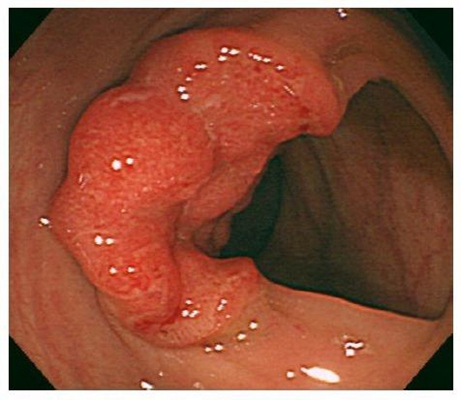

直腸癌圖片

直腸癌晚期症狀 (5)